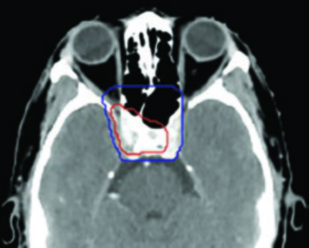

La definición del GTV70 incluye toda la enfermedad macroscópica visible en las imágenes —TC con contraste, RM con gadolinio y PET/CT cuando esté disponible—, así como los hallazgos de la endoscopia. En el sitio primario, el GTV70 abarca el tumor nasofaríngeo con todas sus extensiones: invasión de la base del cráneo, extensión perineural demostrada por RM y cualquier componente en el espacio parafaríngeo o retroestiloideo.

El CTV70 se genera expandiendo el GTV primario entre 3 y 5 mm. En situaciones donde existe alta certeza de los límites tumorales, puede considerarse que GTV equivale a CTV (margen de 0 mm). Cerca de órganos en riesgo críticos (tronco encefálico, quiasma óptico, médula espinal), el margen se reduce o elimina, priorizando la seguridad del paciente. Un principio importante: cuando el tumor invade la órbita ipsilateral, puede sacrificarse el nervio óptico de ese lado para lograr cobertura adecuada, pero nunca el contralateral.

Caso 2: T4N2 EBV positivo

Paciente con enfermedad localmente avanzada, extensión intracraneal a través del foramen oval y seno cavernoso ipsilateral, adenopatías bilaterales en niveles II-V. El GTV70 incluyó el tumor primario con toda su extensión intracraneal visible en RM T1 con gadolinio, así como el conglomerado ganglionar necrótico. El CTV70 se expandió 5 mm en la mayoría de las direcciones, reduciéndose a 0 mm en la interfaz con el lóbulo temporal. El CTV subclínico requirió la inclusión del seno esfenoidal completo, el clivus completo, la cavidad de Meckel bilateral y todos los niveles cervicales bilaterales hasta la grasa posterior a la clavícula en el nivel V.